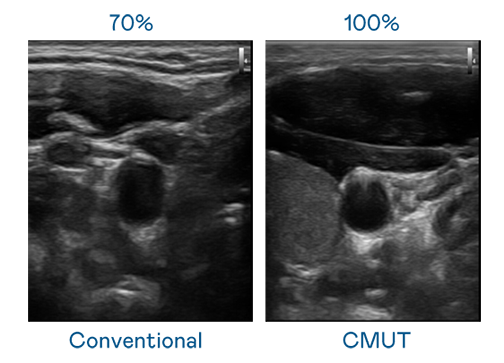

CMUT 技術是一種用電容式微機電元件來產生超音波訊號的技術。與傳統 PZT 壓電式技術相比,CMUT 頻寬增加 30%,更寬頻的超音波訊號讓影像解析度大幅提升,是實現高影像品質醫療超音波掃描、促進精準醫療發展的關鍵技術。

大頻寬帶來超清晰影像

超音波影像的解析度高低,首先取決於探頭能發出的訊號頻寬。BG大游 CMUT 可提供高清晰的超音波訊號,提供高頻寬、高靈敏度、影像紋理細節更高的超音波影像,協助醫護人員縮短影像判讀時間及利用精準的醫療影像進行診斷。